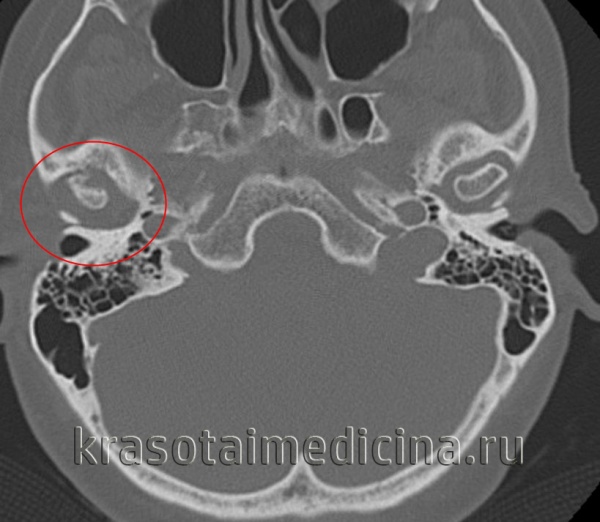

4. КТ при ревматоидном артрите височно-нижнечелюстного сустава (ВНЧС):

• КТ в костном окне и КЛКТ:

о В ранней фазе заболевания рентгеновские признаки отсутствуют

о Ранние изменения: генерализованная остеопения мыщелка и височного компонента

о Эрозия суставного возвышения и передней-верхней медиальной поверхности мыщелка:

- Возможна тотальная деструкция мыщелка и суставного возвышения

- Часто возникает вторичное дегенеративное заболевание сустава (ДЗС) с субхондральными эрозиями; РА сложно отличить от ДЗС

о ± субхондральный склероз о ± поздний фиброз или костный анкилоз

о ± сопутствующее смещение диска